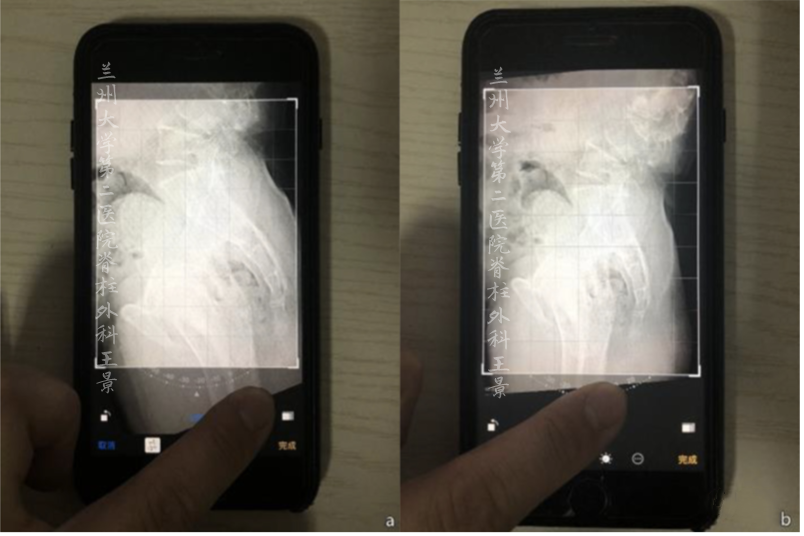

利用iPhone自带照片编辑功能

随意测量脊柱各种角度参数

掏出iPhone,尽量正对拍摄

打开照片,进入编辑模式

手指按着屏幕旋转照片

iOS自带的功能

图片旋转时会显示网格线及旋转角度

顺时针/逆时针旋转分别显示±°

精度为1°